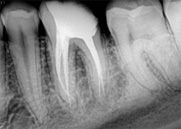

antes depois